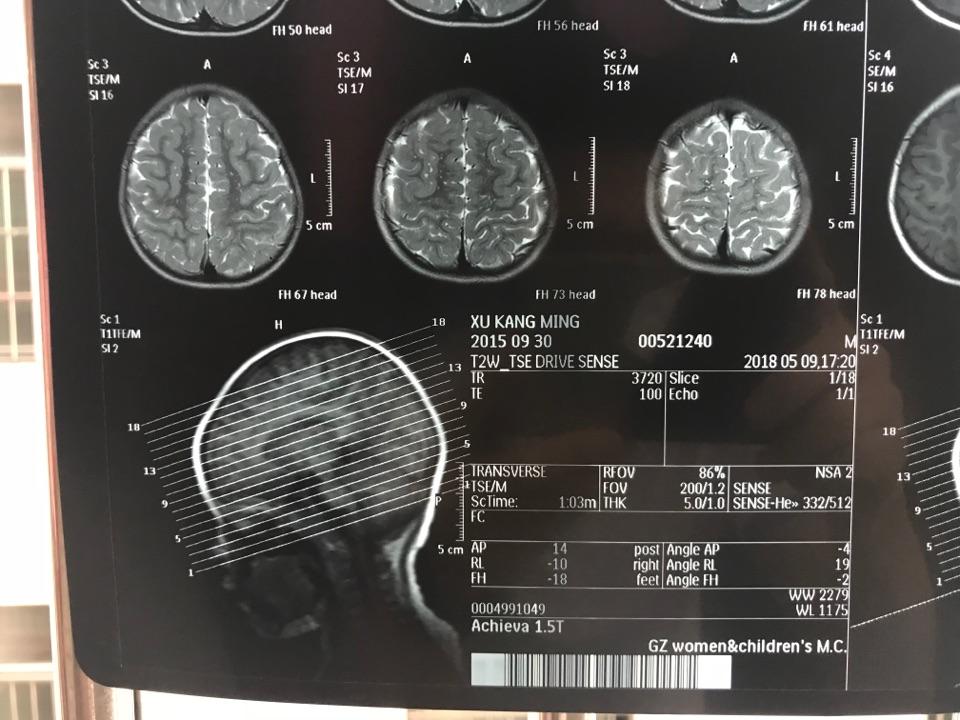

头颅ct:1.左侧半卵圆中心腔隙性脑梗死.2.皮层下动脉硬化性脑病

图片尺寸2666x1999